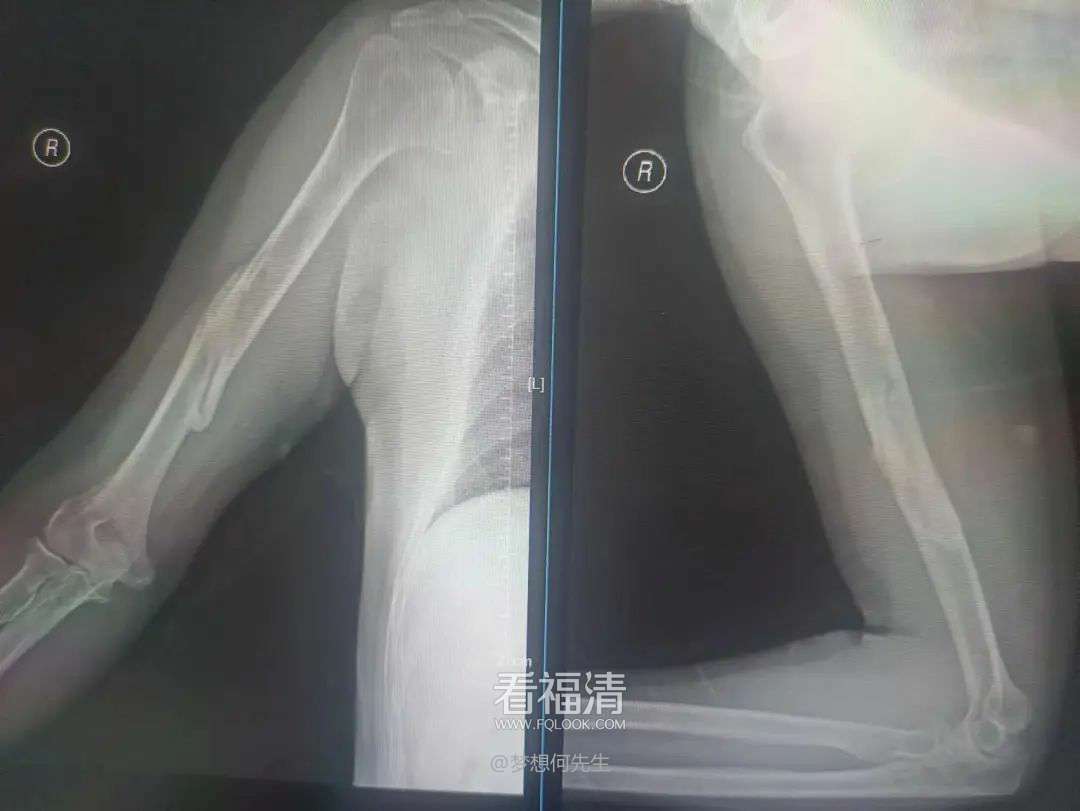

患者为53岁男性,因不慎跌倒,右上臂遭受重创,出现明显的畸形、肿痛以及活动受限。他迅速前往当地医院寻求治疗,经过详细的拍片检查后,被诊断为右肱骨干多段骨折。对此,医师原本建议通过手术治疗来确保患者的康复。然而,该患者由于患有肝硬化,导致凝血功能严重受损,无法接受手术治疗。因此,在伤后四日,患者转至福清市第五医院,希望找到更为合适的保守治疗方案。

第一次拍片

复位后拍片

王征勇接诊后,凭借丰富的临床经验,对患者的病情进行了全面而细致的评估,采用手法复位结合小夹板外固定的方式来进行治疗。随后的影像学检查复查结果显示,患者的骨折对位对线情况良好,但有一处较大的骨片出现了分离移位。王征勇再次进行了审慎的评估,认为当前的对位对线状态是适宜的,可以继续采取保守治疗措施。